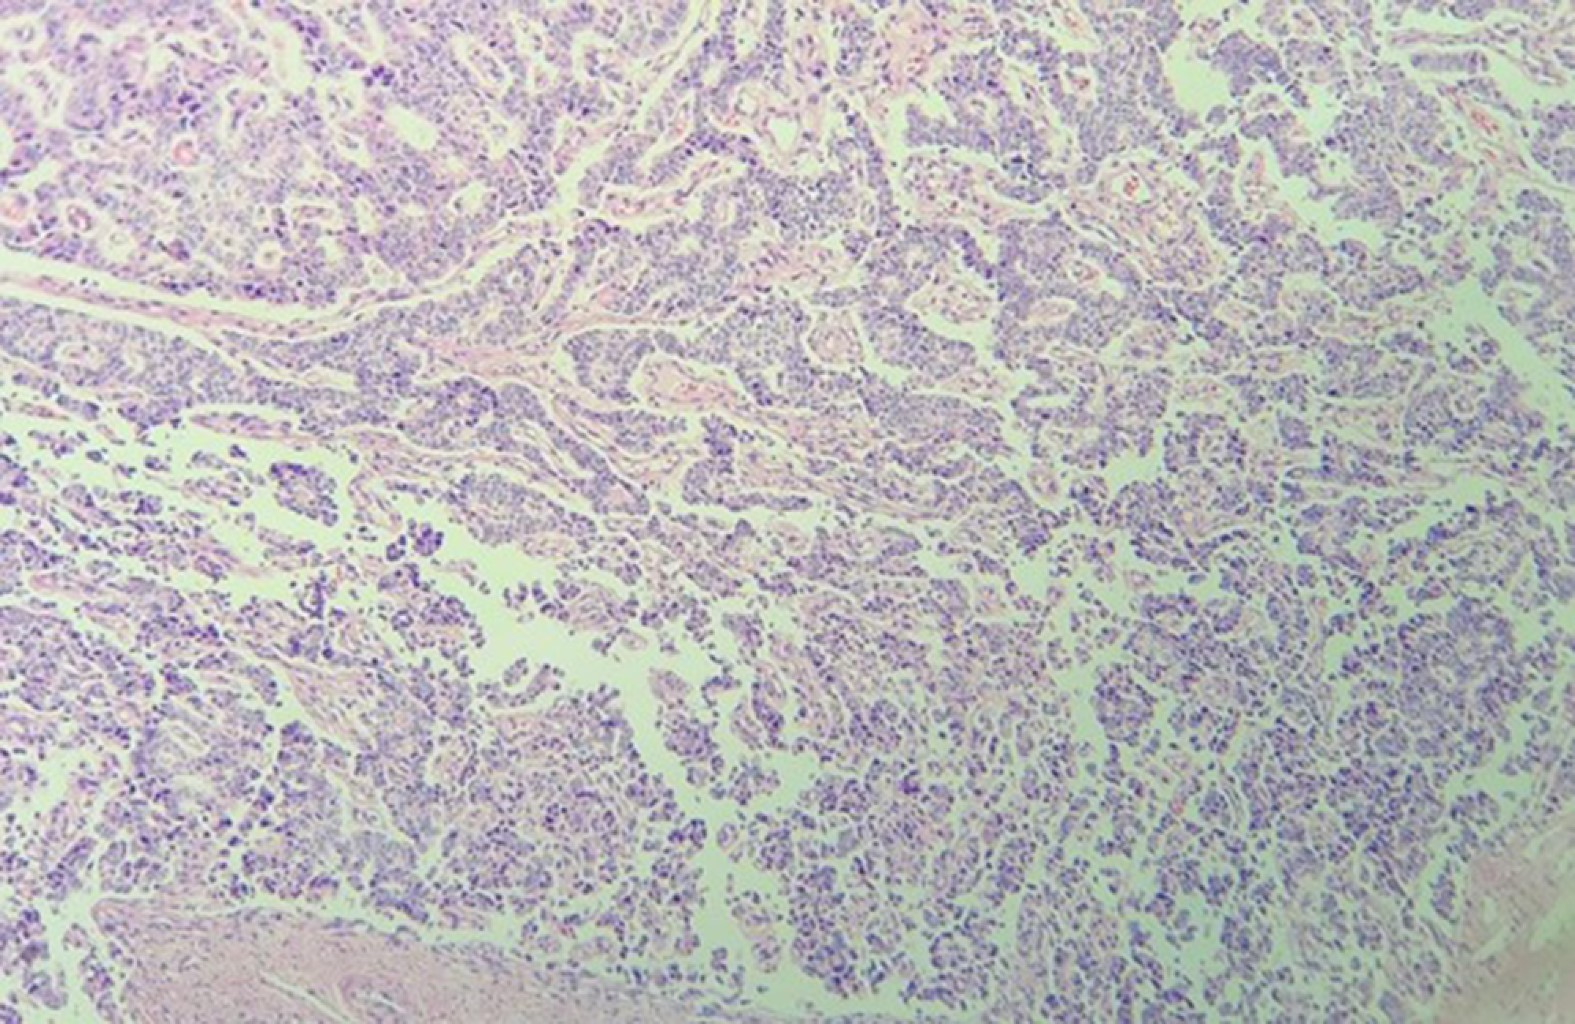

Histopathology Typical carcinoid Atypical carcinoid |

18 (60) 12 (40) |